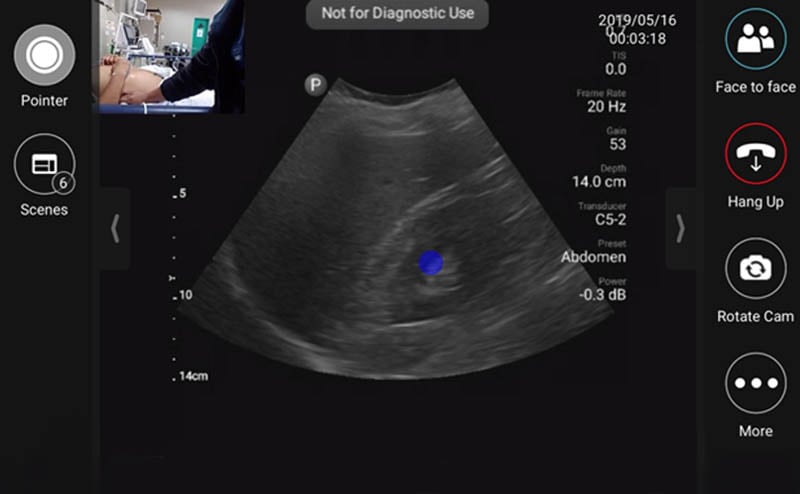

EUS_10-2024-Article1-1.jpgFigure 1. Tele-ultrasound platform as visualized by remote user providing diagnostic/procedural assistance

During the initial months of the fellowship, onsite support during the fellow’s scanning shifts was provided by volunteer visiting instructors from the US. Following this initial period, visiting instructors were not always present in Lima, however fellows could utilize the built-in tele-ultrasound software on the handheld ultrasound device to contact a pool of on-call physicians during their required ultrasound scanning shifts. The inaugural year of the fellowship we primarily relied on tele-ultrasound to provide live support during the fellow’s self-directed scanning shifts whenever questions arose.